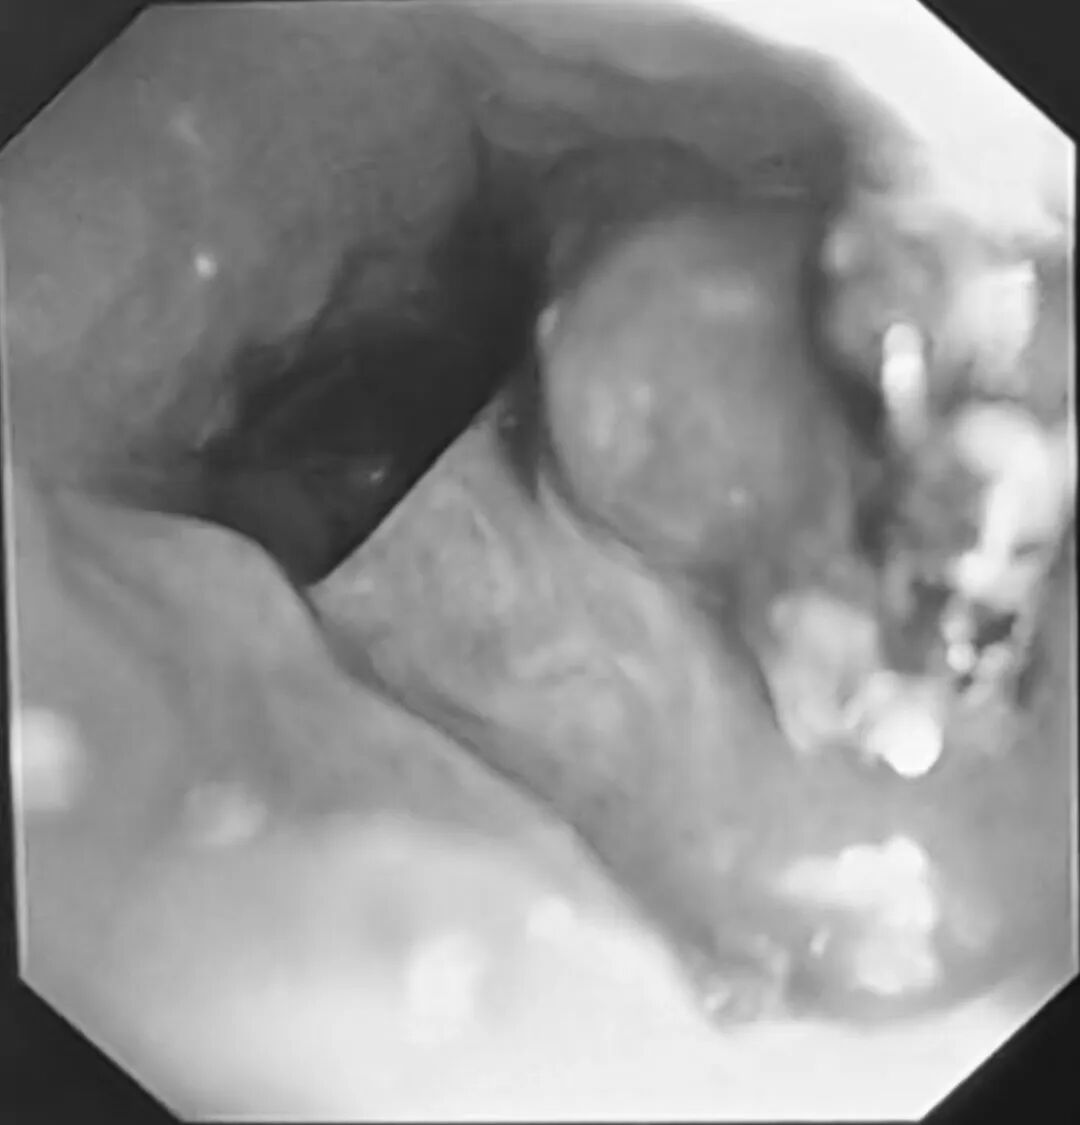

小刘气管插管后,气管镜经过隆突,刚探入右主支气管,屏幕上就出现了异样——大量黄白色脓性分泌物附着在管壁,几乎堵住了视野。王永彬小心操控镜子,一边吸引一边推进,吸除分泌物后,一个被鲜红色肉芽组织紧紧包裹的异物逐渐显露出来,正卡在右上叶支气管开口处,锋利的针头已经深深的嵌入进周围的组织中。

三个月的时间,人体自身的防御机制试图将这个“不速之客”包裹起来。增生的肉芽组织像绳索一样,把图钉牢牢缠住,周围黏膜充血水肿,轻轻一碰就容易出血。

王永彬没有急于下手,他先调整镜头角度,从多个方向观察异物与管壁的关系,判断肉芽组织的范围和质地,然后用活检钳从边缘开始,一点点松动包裹异物的肉芽,像拆解一个缠绕紧密的线团。他每松动一下,都要停下来观察有无活动性出血。待异物松动到一定程度,他换用异物钳,轻轻夹住图钉的边缘,尝试旋转角度。但图钉卡得太紧,他又换用异物套环,从另一侧套住图钉,配合异物钳,一拉一推,反复调整,终于将这枚直径约1厘米的图钉完整取出。